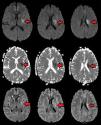

Caso clÃnicoUn paciente masculino de 57años de edad, sin otro factor de riesgo cardiovascular que ex-tabaquismo (22paquetes/año, suspendiendo 14años atrás), ingresa a nuestra institución presentando un cuadro de 45min de evolución consistente en disartria severa, paresia facial derecha severa y paresia braquicrural derecha leve. La primera evaluación médica fue realizada por profesionales de la guardia de emergencias, quienes refirieron que el paciente padecÃa afasia. Veinte minutos tras su ingreso, el puntaje de ictus del NIHSS evaluado por un neurólogo era de 6 (disartria 2 puntos, paresia facial 2, paresia braquial 1, paresia crural 1). La presión arterial (PA) de ingreso fue de 150/90. Con 60min de evolución se realizó una tomografÃa cerebral (TC) con angiotomografÃa (ATC) cerebral (fig. 1) y de vasos de cuello que no demostró sangrado ni lesión isquémica evidente, logrando un puntaje de Alberta Stroke Programe Early CT Score (ASPECTS)1 de 10. En la ATC cerebral no se observó obstrucción, y el puntaje Collateral Score2 fue de 3. En la ATC de vasos de cuello no se observaron estenosis ni lesiones ateroscleróticas. Una reevaluación realizada a las 1:30h de evolución constató una mejorÃa espontánea del cuadro clÃnico, con una reducción de NIHSS a 3 (disartria moderada 1, paresia facial moderada 1, paresia braquial derecha leve 1) en contexto de PA 150/80. Como parte del protocolo de atención, el paciente contaba con dos vÃas periféricas antebraquiales (una en cada brazo) con un goteo lento de solución fisiológica para asegurar su permeabilidad. En ese momento, familiares acompañantes refirieron que minutos antes de la evaluación se hallaba completamente asintomático sin déficit para ellos evidente. Ante tal revelación, llevando 2h de evolución, se realiza maniobra de Trendelenburg y apertura de la infusión de solución fisiológica «a chorro», elevándose la PA a 170/90 y desapareciendo todo déficit neurológico. Media hora después, al agotarse los reservorios de solución fisiológica, y aunque permanecÃa en posición de Trendelenburg, el cuadro deteriora nuevamente volviendo al estado clÃnico inmediatamente anterior con NIHSS de 3, esta vez en contexto de PA 160/80. Se repone infusión de solución fisiológica y el cuadro nuevamente evoluciona favorablemente con NIHSS de 0 y PA de 176/90. El paciente permanece en monitoreo estricto y clÃnicamente estable hasta cumplidas las 3h de evolución, donde a pesar de infusión de solución salina y posición de Trendelenburg la presión arterial desciende a 160/90 y el NIHSS deteriora a 3, presentando siempre el mismo déficit clÃnico (disartria leve-moderada, paresia derecha facial moderada, paresia braquial derecha moderada). Considerando la posibilidad de una trombosis suboclusiva de pequeña arteria con perfusión de miseria (dependiente de PA elevada), se decidió iniciar infusión de Alteplase (dosis plena total 72mg, 10% en bolo endovenoso y el 90% restante en infusión continua a lo largo de una hora). Durante la infusión la PA osciló entre 165 y 158 (sistólica) y 90 a 86 (diastólica). Durante toda la infusión el paciente permaneció en decúbito dorsal a 0 grados respecto al suelo. La evaluación secuencial de NIHSS fue: 3 puntos (basal), 2 puntos (15min de infusión), 0 puntos (30 y 45min de infusión). Al final de la infusión, con PA 160/80, se objetiva nueva fluctuación del cuadro clÃnico, presentando nuevamente NIHSS de 3. A pesar de que el cuadro clÃnico sugerÃa una topografÃa lacunar, dado que al ingreso del paciente el médico que le recibe refirió que el paciente presentaba afasia, ante la posibilidad de estenosis de ramas distales de la arteria cerebral media izquierda se decide realizar angiografÃa digital en busca de estenosis, procedimiento realizado a las 5h 30min, descartando con dicho estudio la presencia de estenosis silviana proximal y distal. Finalizada la angiografÃa digital, se constata que el paciente presentaba un NIHSS de 0 puntos. Por último, desde la sala de hemodinamia fue trasladado para la realización de un protocolo corto de resonancia (secuencias FLAIR, susceptibilidad magnética, difusión y ADC) donde se apreció una lesión isquémica aguda en topografÃa lenticulocapsular izquierda de 26mm de diámetro máximo con restricción de la difusión, ya visible nÃtidamente en secuencia FLAIR, y sin sangrados según susceptibilidad magnética (fig. 2); la RM fue realizada habiendo transcurrido 6h y 40min desde el inicio del cuadro. El paciente ingresó a la unidad de cuidados crÃticos a las 7h de evolución para continuidad de su atención y monitoreo. Se logró estabilizar la presión mediante infusión de solución fisiológica e infusión continua de noradrenalina. A las 24h, sin mediar complicación alguna ni fluctuaciones en presión arterial, el paciente presentaba un NIHSS de 3 (disartria leve, paresia facial central derecha leve, paresia del miembro superior derecho leve). La TC realizada a las 24h post-trombólisis como control rutinario (fig. 3) demostró la presencia de una lesión hipodensa lenticulocapsular izquierda en idéntica topografÃa a la evidenciada en la resonancia magnética, y no se observaron lesiones compatibles con sangrado. Durante la internación se realizó un ecocardiograma transtorácico que informó diámetros, espesores y función del ventrÃculo izquierdo conservado, sin valvulopatÃas ni dilatación auricular izquierda. El alta fue otorgada tras cumplir 6dÃas de internación, y se indicó continuar en forma ambulatoria con ácido acetilsalicÃlico 100mg/dÃa, atorvastatina 20mg/dÃa y enalapril 5mg/dÃa. Su NIHSS al alta fue de 1 (por presentar solo disartria leve). Al mes del evento el paciente ya no presentaba disartria, su NIHSS era de 0 y su puntaje en la escala modificada de Rankin era 0. Se solicitó un monitoreo Holter ambulatorio, pero el paciente no retornó a consulta posteriormente.